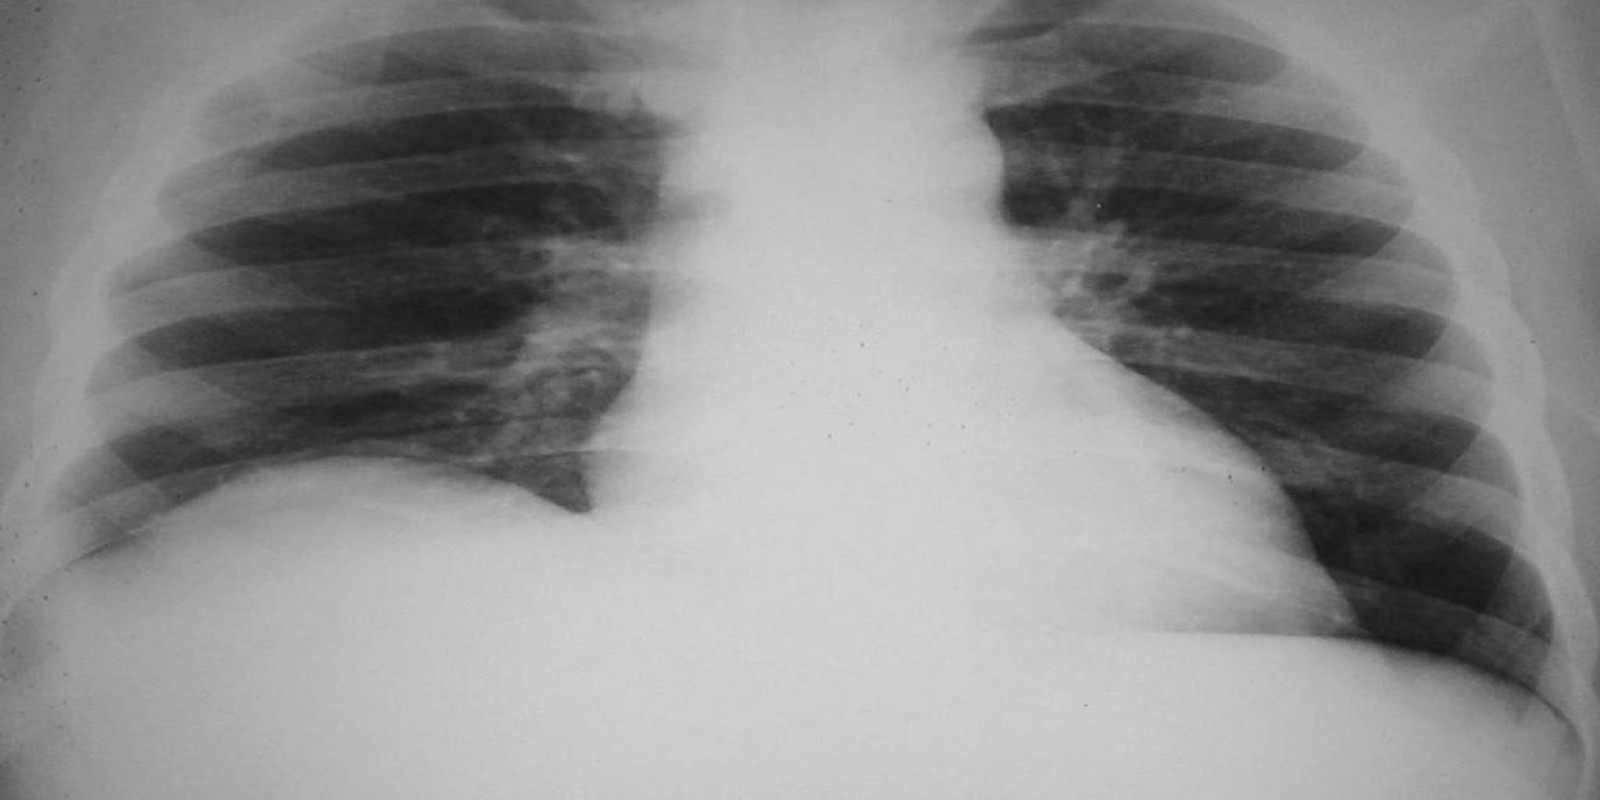

Abscesso Hepático

Liver abscess

Caso Código 042C de Abscesso Hepático

Cod.: 042C